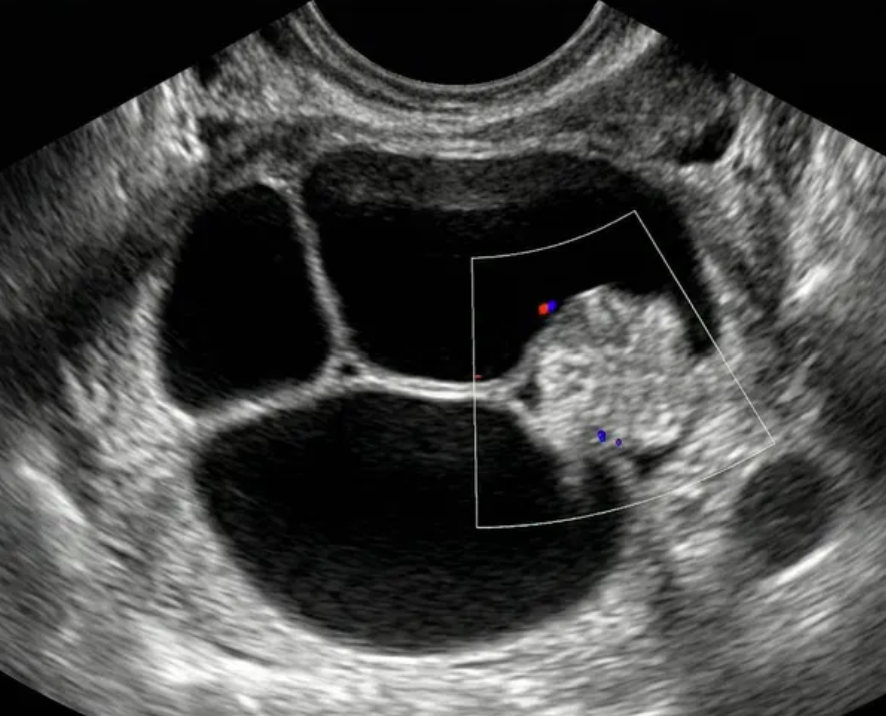

O-RADS US 4 — Risco Intermediário

Risco: 10-<50%Cisto multilocular sem componente sólido ≥ 10 cm ou com IC = 4, cisto unilocular/multilocular com componente sólido, lesão sólida com superfície lisa e IC = 2–3.

Cisto multilocular, sem componente sólido

Cisto unilocular com componente sólido

Cisto multilocular com componente sólido

Lesão sólida

Conduta

Opções de imagem incluem US com especialista (se disponível) e RM (com O-RADS MRI score), de acordo com o protocolo do ginecologista-oncologista. Atendimento pelo ginecologista com consulta ao ginecologista-oncologista ou exclusivamente pelo ginecologista-oncologista.